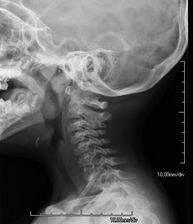

- RX Columna cervical

Técnica mediante la cual, utilizando rayos X, se obtienen imágenes de la columna cervical para su estudio. Indicaciones: traumatismo, contractura cervical, dolor articular.

Técnica mediante la cual, utilizando rayos X, se obtienen imágenes de la columna cervical para su estudio. Indicaciones: traumatismo, dolor cervical.